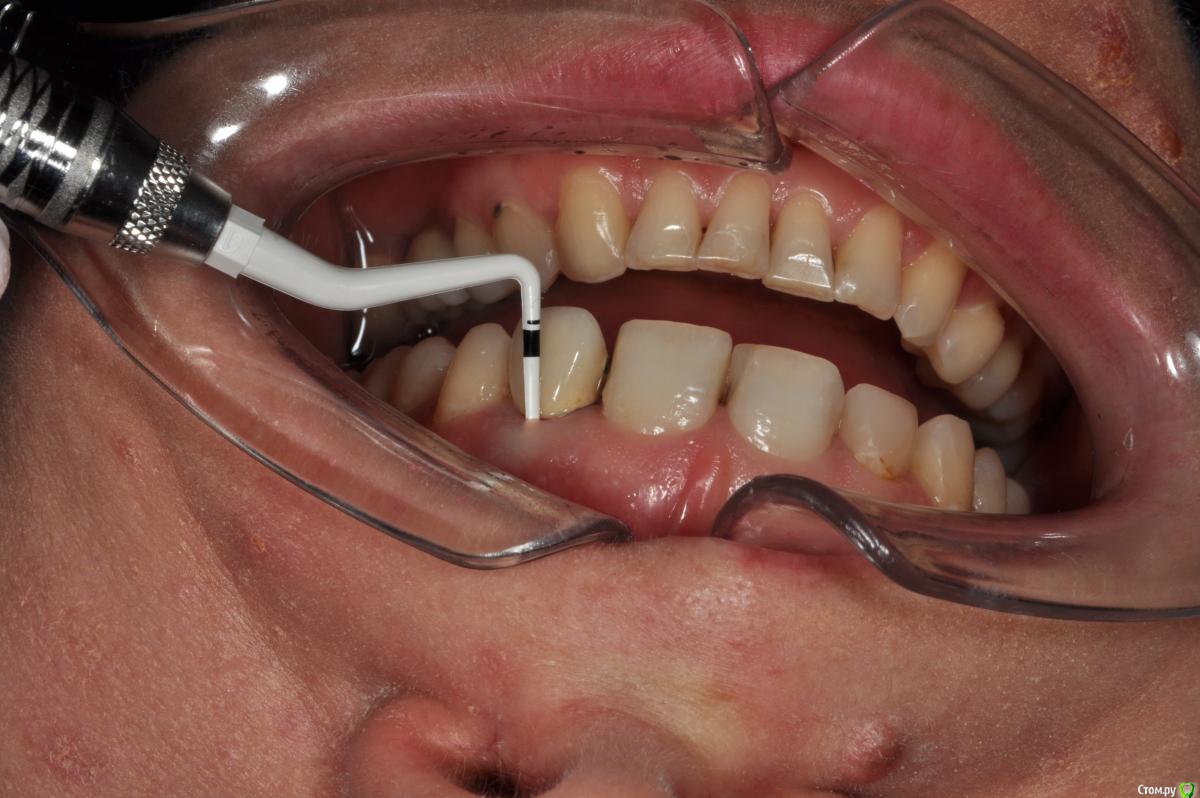

Пациентка 37 лет, не курит, соматически здорова. Частое выпадение ЛШКВ с коронкой. Диагностирована  фрактура вестибулярной стенки кореня зуба 22. Линия улыбки высокая. Биотип толстый.  Отсутствие вестибулярной пластинки, карман 8мм без ексудата.  Латеротрузия через 22.